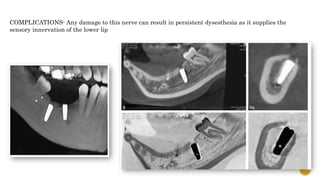

COMPLICATIONS- Any damage to this nerve can result in persistent dysesthesia as it supplies the

sensory innervation of the lower lip

 Also knows as ISCHEMIC ZONE.

 MANDIBULAR CANAL

 Importance- carries inferior alveolar neurovascular bundle

 Variations-